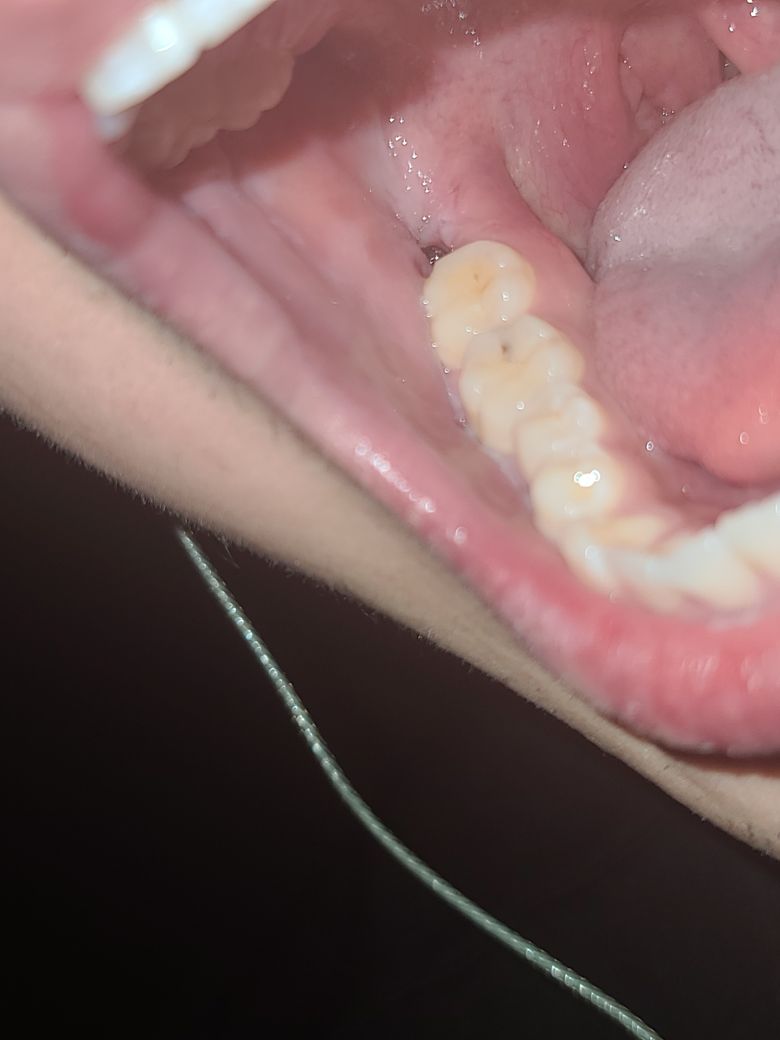

왼쪽 사랑니의 경우 반쯤 잇몸에 묻혀 있어 위생 관리가 쉽지 않아 충치나 잇몸병이 생기기 쉬우므로 미리 빼주는 것이 좋습니다

오른쪽 사랑니 보다 덜 누워있거나 매복이 덜 되어있는 경우 발치가 더 쉽습니다

사진 상으로 보았을 때는 결국에 문제를 일으킬 것으로 보입니다. 해당 사랑니 주변에 음식물이 쌓이면서 사랑니 뿐만 아니라 앞쪽 어금니도 손상시킬 것으로 보입니다. 따라서 치과 방문 후 발치를 하는 것이 좋습니다.